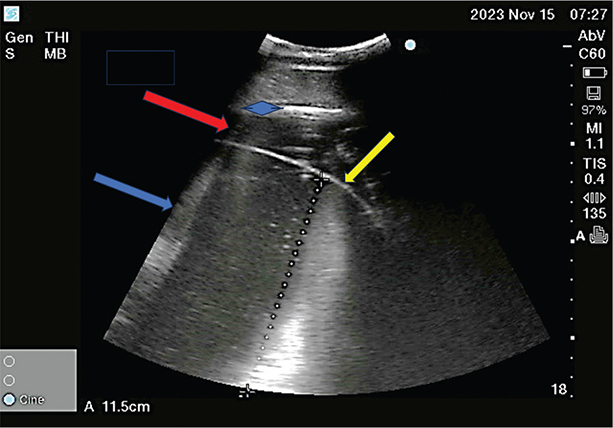

Five days after initial evaluation, the mare appeared to have a wider ventral distribution of abdominal distension and was referred due to concern for impending body wall injury. Altrenogest was discontinued and mare was admitted to the referral hospital on day 230 of pregnancy. Physical examination revealed marked abdominal distension and a plaque of ventral abdominal edema (Figure 1). Transrectal palpation and ultrasonography revealed domed gravid uterus extending well above mare’s pubic level. The CTUP was 0.6 cm (considered normal for this stage of pregnancy).16 Transabdominal ultrasonography revealed turgid amniotic membrane, lacking undulations (Figure 2), suggesting increased intra-amniotic fluid pressure. The largest umbilical vessel within the amniotic cavity was 1.13 cm in diameter (Figure 3A); fetal urachus had increased luminal diameter (Figure 3B). Fetal bladder measured 6 x 5 cm and was distended with anechoic fluid. Doppler was used to identify the urachus by lack of blood flow compared to umbilical vessels (Figure 4). Fetal heart rate was 90 beats per minute and pericardial effusion was suspected due to the appearance of hypoechoic fluid around beating heart muscle. Again, the fetus’s mouth was open. Additionally, ultrasonography of mare’s ventral abdomen revealed marked subcutaneous edema, consistent with impaired lymphatic and venous drainage secondary to gravid uterus weight. A presumptive diagnosis of hydrops was made based on these clinical findings. Termination of pregnancy and induction of parturition was elected to salvage the mare.

Figure 2. Transabdominal ultrasonographic image of uterus: amniotic membrane (yellow arrow); amniotic cavity (blue arrow); allantoic cavity (red arrow); chorioallantois and endometrium demarcation (blue diamond) where CTUP was measured; note lack of undulations in amniotic membrane.